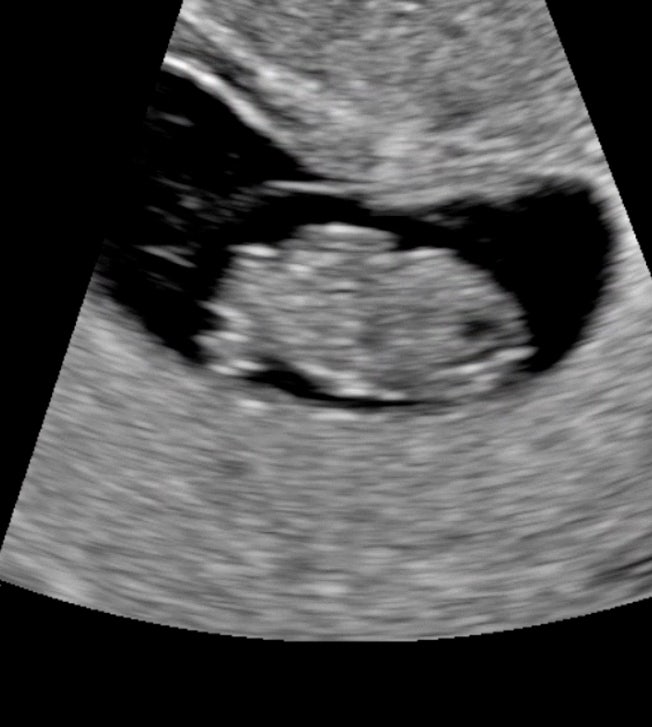

✨임신19-23주차일상/정밀초음파/전치태반/임산부수영/

20주-24주차에는 태아 정밀 초음파를 보는 시기예요 1차검진때 목투명대 등 기본 검사를 했다면 정밀초음파...